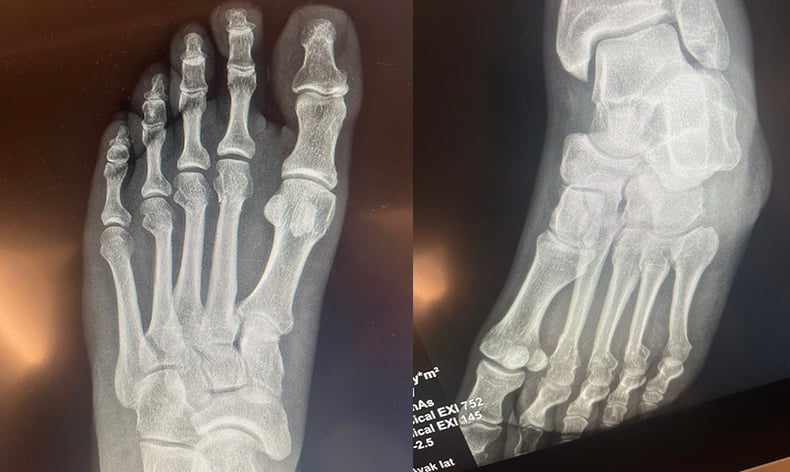

Özgür Özel, röntgen filmlerini paylaştı

CHP Grup Başkanvekili Ali Mahir Başarır, geçen hafta TBMM’deki özel oturum öncesi gazetecilere yaptığı açıklamada, CHP Genel Başkanı Özgür Özel’in evde geçirdiği kaza sonucu ayağında ufak çaplı kırılma olduğunu duyurmuştu. Özel’in ayağında oluşan kırık hakkında sosyal medyada, Özel’in ‘ayağından vurulduğu’ iddiaları yer almıştı. Özel, tartışmalara ilişkin ayağının röntgen filmlerini paylaştı.